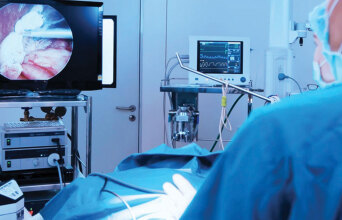

Τα συστήματα CONTOUR®NEXT αποτελούν τον ιδανικό σύμμαχο κάθε ατόμου με διαβήτη αλλά και των επαγγελματιών υγείας που τα υποστηρίζουν